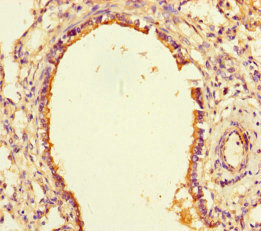

ApplicationELISA, IHC, IF; Recommended dilution: IHC:1:20-1:200, IF:1:50-1:200